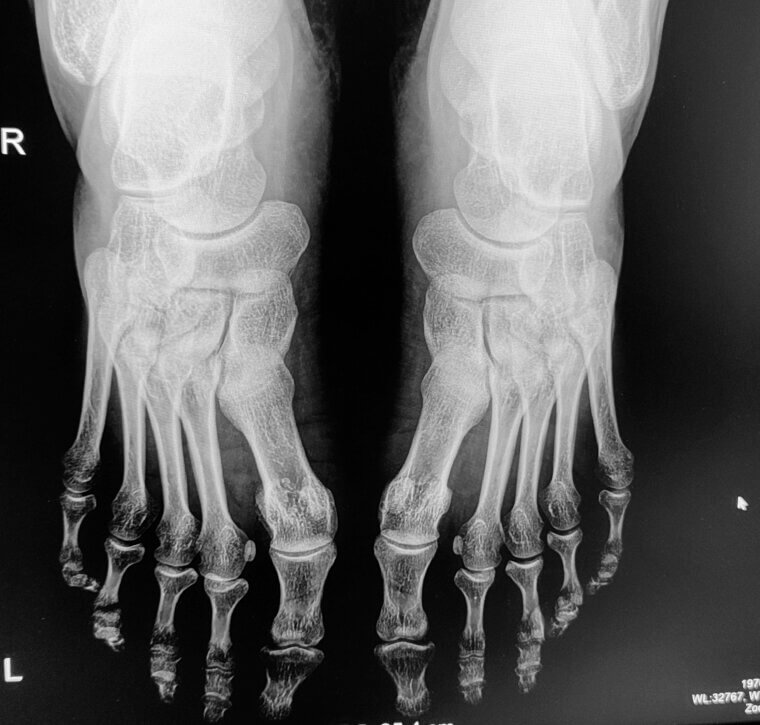

The Horrors of Varicose Veins

One of the more visual effects of sitting too long is varicose veins. Sitting all day causes pressure to build up in your legs. Over time, this leads to bulging, visible veins that are uncomfortable, too. Getting up and walking around helps relieve this pressure.

Blood Clots and Deep Vein Thrombosis

One of the best reasons to get up and stretch or walk around is to cut down your risk of blood clots and deep vein thrombosis. This is caused by the blood pooling in your legs while sitting. In rare cases, this causes clots that can be serious.